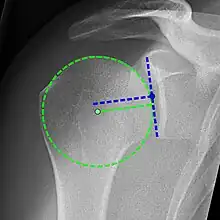

Xray

X-ray projectional radiography cannot directly reveal tears of the rotator cuff, a 'soft tissue', and consequently, normal X-rays cannot exclude a damaged cuff. However, indirect evidence of pathology may be seen in instances where one or more of the tendons has undergone degenerative calcification (calcific tendinitis). The humeral head may migrate upward (high-riding humeral head) secondary to tears of the infraspinatus, or combined tears of the supraspinatus and infraspinatus.[51] The migration can be measured by the distance between:

- A line crossing the center of a line between the superior and inferior rims of the glenoid articular surface (blue in image).

- The center of a "best-fit" circle positioned over the humeral articular surface (green in image)

Normally, the former is positioned inferiorly to the latter, and a reversal therefore indicates a rotator cuff tear.[51] Prolonged contact between a high-riding humeral head and the acromion above it may lead to X-ray findings of wear on the humeral head and acromion; secondary degenerative arthritis of the glenohumeral joint (the ball and socket joint of the shoulder), called cuff arthropathy, may follow.[50] Incidental X-ray findings of bone spurs at the adjacent acromioclavicular joint may show a bone spur growing from the outer edge of the clavicle downward toward the rotator cuff. Spurs may also be seen on the underside of the acromion, once thought to cause direct fraying of the rotator cuff from contact friction, a concept currently regarded as controversial.